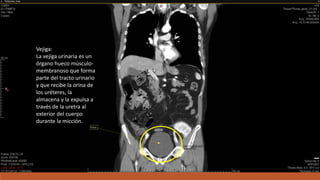

Vejiga:

La vejiga urinaria es un

órgano hueco músculo-

membranoso que forma

parte del tracto urinario

y que recibe la orina de

los uréteres, la

almacena y la expulsa a

través de la uretra al

exterior del cuerpo

durante la micción.